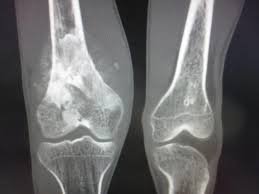

Mitos dan Fakta seputar Kanker Tulang

Jenis kanker yang terbentuk pada jaringan tulang dan termasuk dalam kategori kanker langka, namun kanker tulang gejala dan pemahamannya yang masih terbatas di masyarakat sehingga menjadi memiliki mitos seputar penyakit ini pun berkembang. Yuk memahami mana yang benar dan mana yang sekedar mitos sangat penting agar tidak salah kaprah dalam menyikapi kondisi ini.